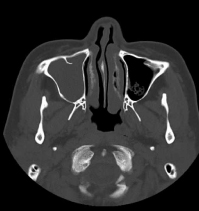

CT検査

整形外科領域

- 四肢

- 骨折・脱臼などの外傷

- 副鼻腔炎・乳突蜂巣炎(聴器)など